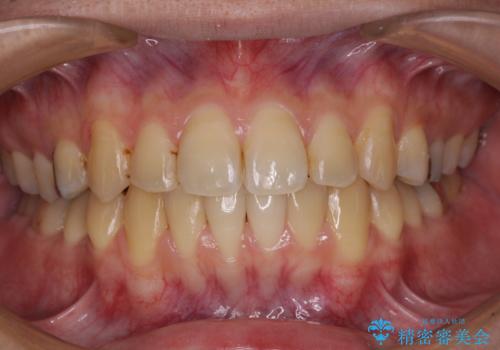

前歯のクロスバイトをインビザラインで矯正治療

- 前歯のデコボコとクロスバイトを気にして来院された患者様です。

前歯を早く整えたいとの希望があったので、ワイヤー矯正にて短期間でクロスバイトを解消し、その後インビザラインにて整えることとしました。

インビザラインによる前歯のクロスバイト改善におけるリスクとして、前歯歯髄充血・歯髄壊死が挙げられます。

ワイヤー矯正を併用する目的として、短期間でデコボコやクロスバイトを改善する他に、歯髄充血リスクを低減させるというものがあります。